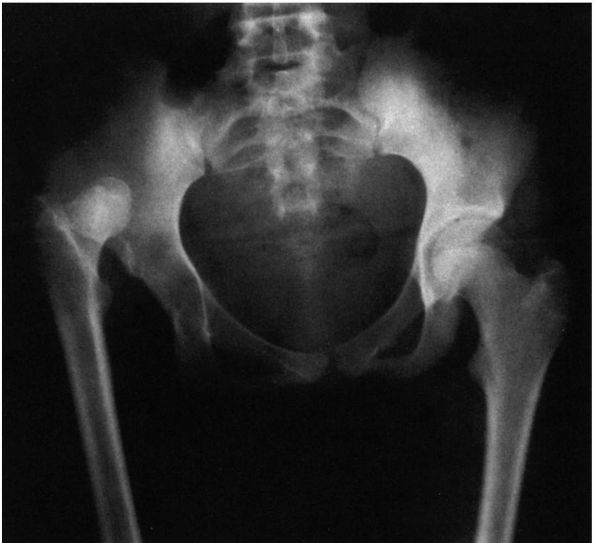

is important to appreciate that the normal concave shape of the

acetabulum develops in response to the presence of a spherical femoral

head. Experimental studies in animals as well as observations in humans

with unreduced congenital hip dislocations show that the acetabulum

does not develop its normal concave shape. Instead, with a complete

dislocation, the triradiate cartilage grows normally, and hence the

innominate bone reaches its normal length (Figure 15-5);

but the acetabular cartilage atrophies and degenerates, and the

acetabulum appears flattened. The depth of the acetabulum increases

![]() |

|

FIGURE 15-5.

Untreated right congenital hip dysplasia in an adult. Note the lack of development of acetabular shape and depth. No secondary acetabulum exists. The left hip is normal. |